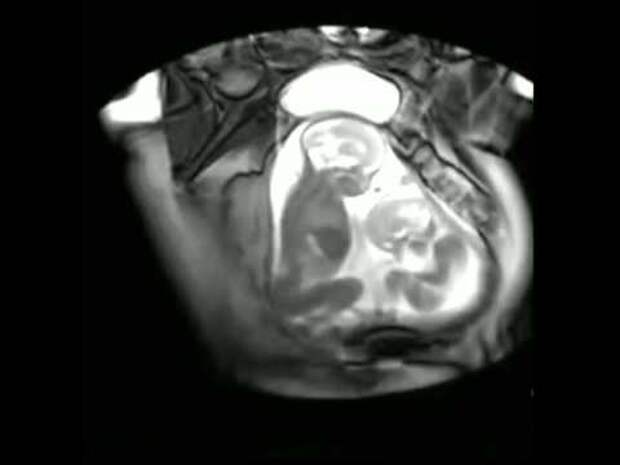

Главное, чтобы рядом был человек, который будет ее поддерживать. Для пары очень волнительно первый раз увидеть своего ребеночка!Они ждут этого момента с замиранием сердца. МРТ можно делать после первого триместра беременности. Только представьте волнение отца и матери, когда у них есть возможность первый раз увидеть своего ребеночка. Эта пара увидела не одного ребенка, а двух! Они станут родителями прекрасных близнецов. Посмотрите, как малыши дерутся за место внутри мамы. Один близнец очень настойчиво пинает другого ногами, пытаясь освободить себе побольше места. Поразительный процесс! Хотите посмотреть как это происходит? Теперь это доступно благодаря современным медицинским технологиям!